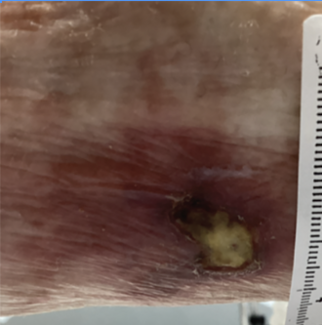

This study evaluated the safety and efficacy of a novel debriding agent comprised of collagenases G and H, and hyaluronate lyase, in chronic wounds.